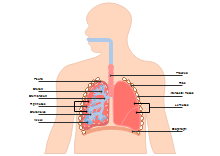

illustrazione scientifica - anatomia umana